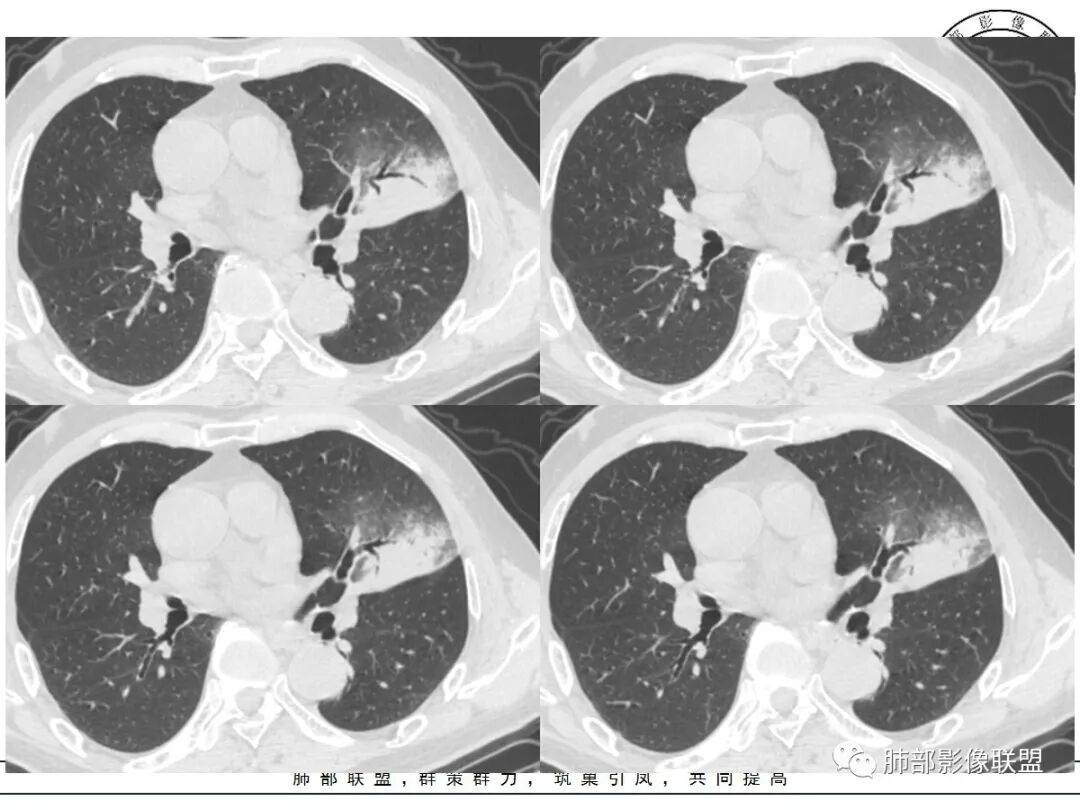

胸膜下实变,周围伴磨玻璃影,长轴与胸膜平行

病灶沿叶间胸膜向内,支气管远端不畅,近端有扩张,所以符合外朝内病变。

外朝内无非是:占位效应,GGO边缘;支气管走形、堵塞的形态,血管,密度及强化;内部的坏死及空洞。

我标示一下,尖后段搭到一部分,前段也占了一点点。

主体在舌段

有占位效应吗?

有,斜裂局部膨隆

边缘膨隆,叶间裂有局部膨出下坠

有膨隆+收缩

密度?

实变为主,加周围模糊GGO

GGO+实变

强化如何?

强化有疑问,前面感觉有低密度的,有些图好像又均匀

不均匀中度强化

不均匀轻中度渐进强化。

整体形态

南边:

外围大,内带小

支气管?

支气管外面堵了,近端有扩张

有堵塞,有狭窄

中远端堵塞,堵塞端圆钝

炎性? 肺炎型肺癌待排